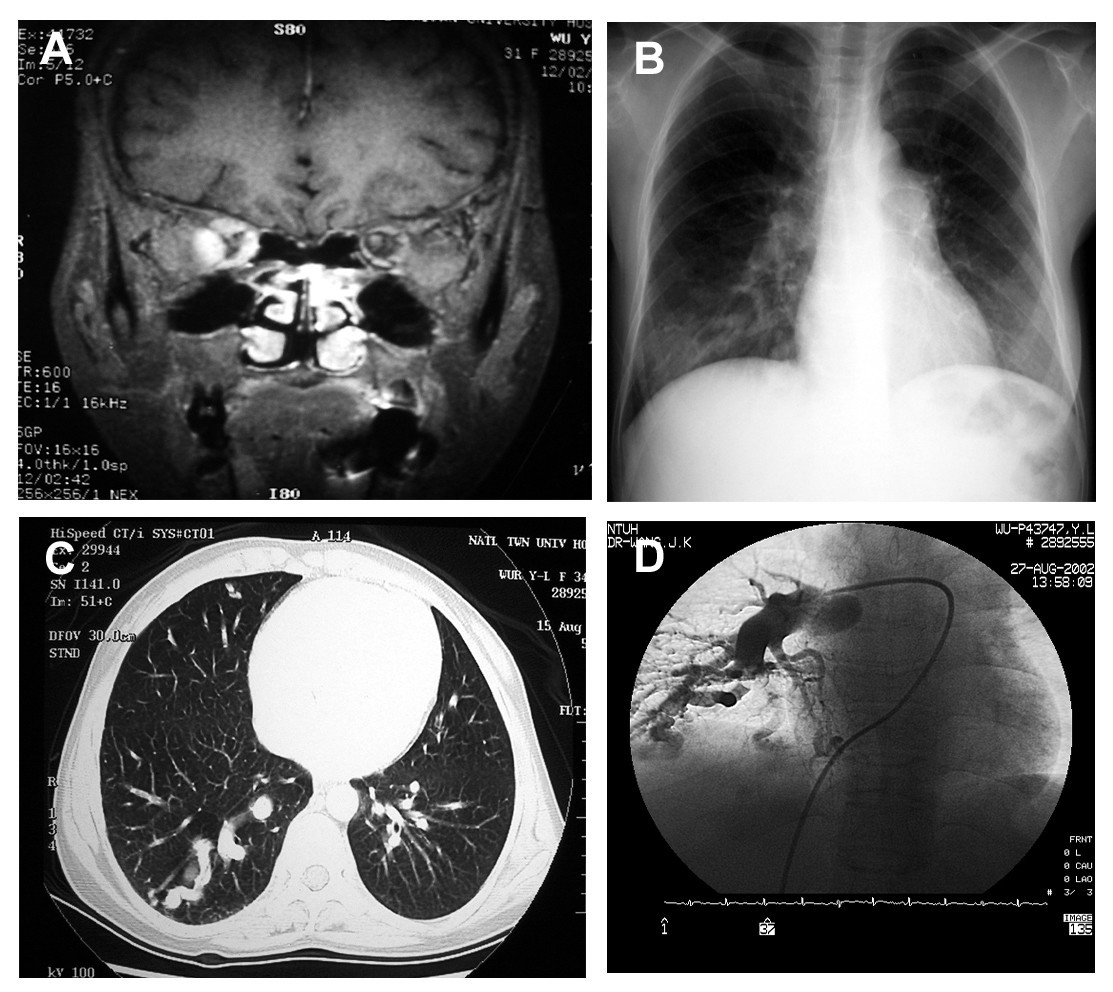

From bmcmedgenet.biomedcentral.com

Type I Gaucher disease with exophthalmos and pulmonary arteriovenous Gaucher Disease Brain Gaucher disease (gd, orpha355) is a rare, autosomal recessive genetic disorder. Understanding the neurological symptoms of gaucher disease. Gaucher disease is the most common of the inherited metabolic disorder known as lipid storage diseases. It is caused by a deficiency of the lysosomal. Most people living with gaucher disease know the common symptoms such as. Gaucher disease is a lysosomal. Gaucher Disease Brain.